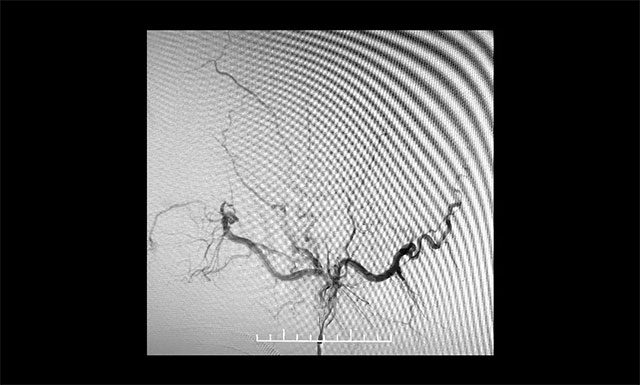

DSA 檢查顯示,左側(cè)天幕區(qū)硬腦膜動靜脈瘺,瘺口血流大,供血來源廣泛,引流靜脈有瘤樣擴(kuò)張。

DSA檢查顯示,左側(cè)天幕區(qū)硬腦膜動靜脈瘺

▲ DSA檢查顯示,左側(cè)天幕區(qū)硬腦膜動靜脈瘺